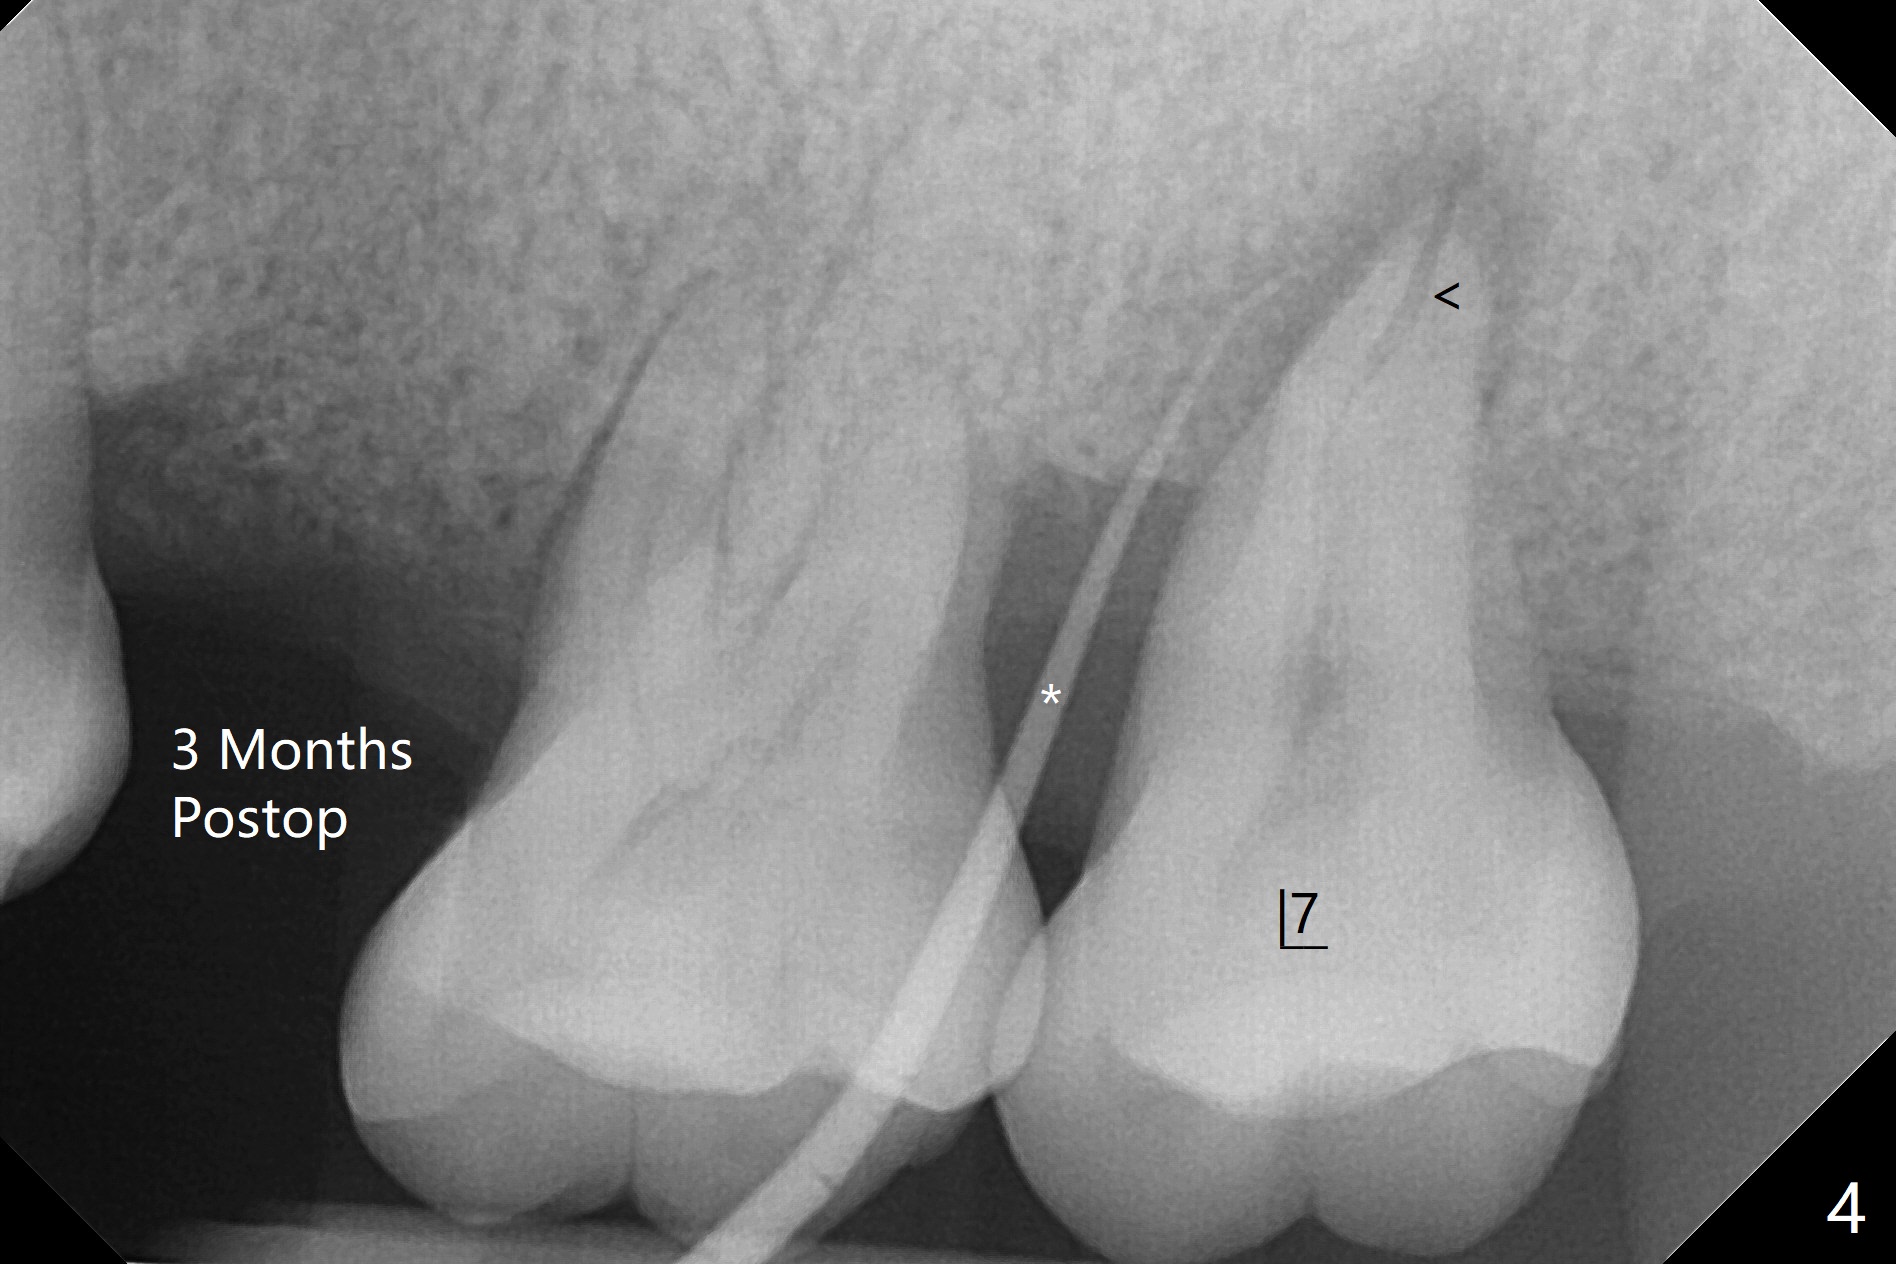

术后二周牙周敷料松动,取出后,伤口尚可(图三)。可能病人用右侧咀嚼,造成右上两个双尖牙松动疼痛,拔出后即刻种植修复,之后她能在右侧咀嚼,而食物撞击左上拔牙创疼痛,无法吃饭。术后三个月左上7疼痛,瘘道,插入牙胶尖(图四:*),根周阴影。其实腭侧根纵裂(图四,五:<),三个月已经发生(图二),可以即刻种植(图六),与5延期种植同时进行,使用导板。